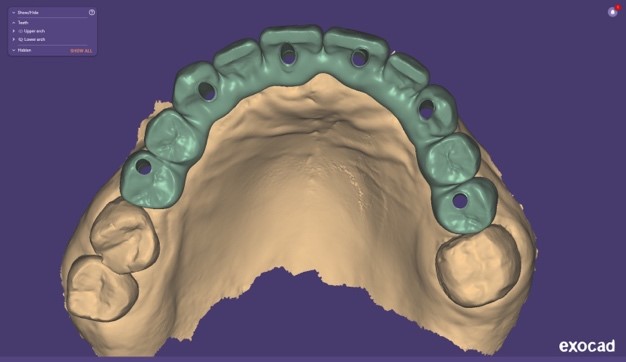

Si procedeva quindi alla scansione degli iPhysio® utilizzando uno scanner intraorale (IS 3600®, Dexis, Envista Holding Corporation, Brea, USA) (Fig. 4 a). Inviavamo i file STL al laboratorio odontotecnico per progettare e realizzare la protesi finale (Fig. 4 b,c,d,e,f).

Progetto CAD finale

Fig. 4(a)

Progetto CAD finale 2

Fig. 4(b)

Progetto CAD finale 3

Fig. 4(c)

Progetto CAD finale 4

Fig. 4(d)

Progetto CAD finale 5

Fig. 4(e)

Progetto CAD finale 6

Fig. 4(f) Progetto CAD finale della protesi.

Il laboratorio odontotecnico utilizzava le più recenti tecnologie CAD/CAM per produrre una protesi dentale personalizzata e di alta qualità che si adattasse perfettamente e garantisse funzionalità ed estetica ottimali. Il concetto iPhysio® facilita il recupero automatico del profilo di emergenza sottogengivale da parte dell'odontotecnico per la realizzazione di soluzioni personalizzate sia con la protesi cementata che con la protesi avvitata (Fig. 5 a,b,c). La paziente tornava per il posizionamento del restauro finale in zirconio avvitato (Fig. 6 a,b).